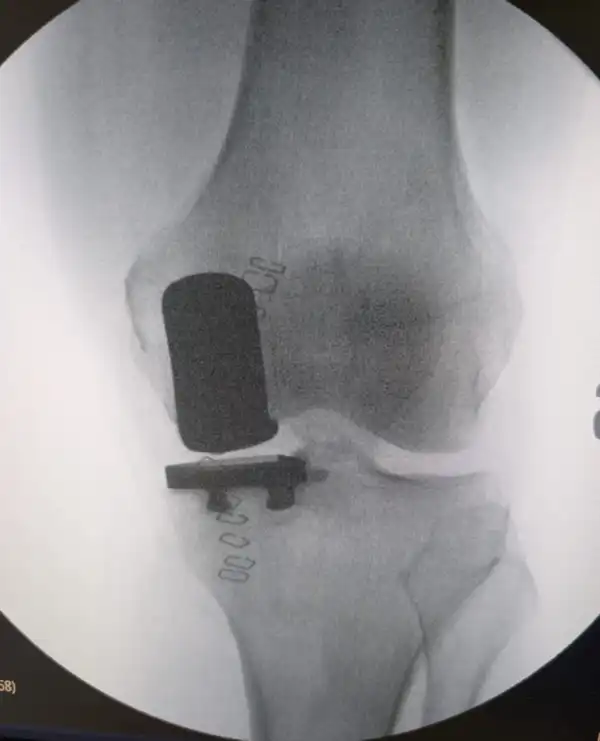

La protesi ginocchio è una soluzione efficace per i pazienti che soffrono di gravi forme di degenerazione articolare, come l’artrosi avanzata, quando i trattamenti conservativi (ad esempio, farmaci, fisioterapia o infiltrazioni) sono controindicati o non hanno portato risultati significativi. Questa procedura prevede la sostituzione dell’articolazione del ginocchio con una protesi artificiale, ripristinando la funzionalità e alleviando il dolore cronico.

Video dimostrativo sull’ artroprotesi di ginocchio, protocollo fast-track,

con evidenza delle fasi chirurgiche principali.